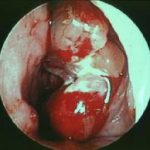

✔ Sialoendoskopi: Küçük kamera ile doğrudan kanal içine bakılarak taşın yerinin tespit edilmesi ve tedavide kullanılması için de tercih edilebilir.

Sialoendoskopi: Küçük bir kamera ve aletlerle taşın kanaldan çıkarılması

Şok dalga litotripsisi: Taşları kırarak küçük parçalar hâline getirip dışarı çıkmasını sağlama

Sialoendoskopi (hem tanı hem tedavi)